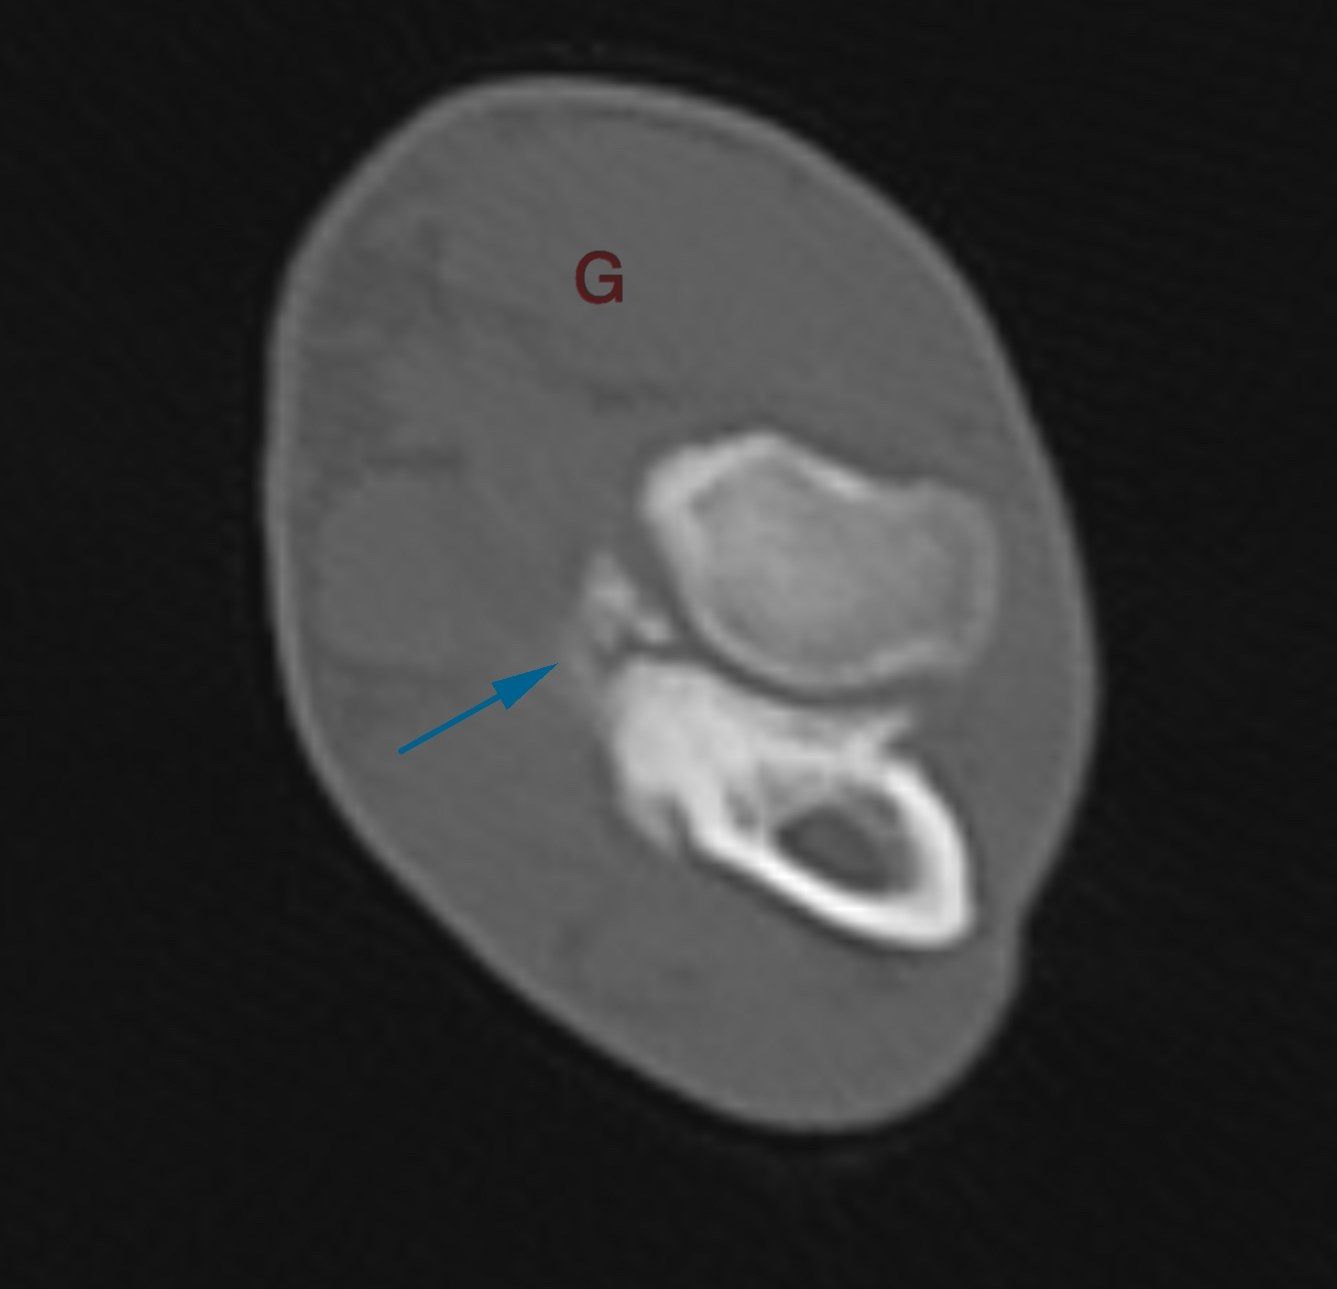

Examens complémentaires - Scanner des coudes et des épaules

Le scanner des coudes et des épaules a mis en évidence une maladie du compartiment médial bilatérale, avec une forte suspicion de fragmentation du processus coronoide médial, et une légère effusion articulaire bilatérale. Les épaules ne montrent pas d'anomalie significative, permettant d'exclure un phénomène d'OCD de l'épaule. Le scanner est l'examen de choix lors de boiterie d'un antérieur inexpliquée chez un jeune. Cet examen permet d'aller plus loin que la radiographie, er permet notamment de supprimer les superpositions osseuses inhérentes à l'anatomie du coude. Le scanner permet en outre d'explorer les cavités centromédullaires et ainsi évincer une hypothèse de panostéite concomitante. Cet examen ne permet en revanche pas d'explorer la surface articulaire, mais bien uniquement l'os sous chondral. L'arthroscopie des coudes est l'examen le plus adapté permettant une exploration complète de l'articulation et la visualisation directe de la surface articulaire, mais ne permet pas l'évaluation de l'os sous chondral. Le scanner, couplé à l'arthroscopie, sont donc les deux examens de choix dans la démarche diagnostique d'une dysplasie du coude chez le chien.